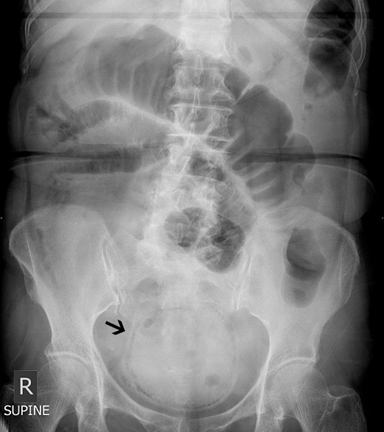

A 73-year-old diabetic female was presented to the emergency department with lower abdominal pain and distension for five days. Physical examination revealed tenderness over her right iliac fossa and supra-pubic region. An abdominal X-ray (Figure 1) revealed a spherical structure in the pelvis in the expected position of the bladder with presence of intramural gas and a provisional diagnosis of emphysematous cystitis was made by the emergency physicians. Urinary catheterization performed yielded clear urine and urine dipstick did not reveal any evidence of urinary tract infection. The patient's abdominal pain and distension worsened and a surgical consult was made. Further history corroborated with the patient's family revealed that the patient has had associated absolute constipation for last five days. The abdominal X-ray was reviewed which also showed a loop of dilated transverse colon. There was suspicion of colonic intestinal obstruction. Computed tomography (CT) scan of her abdomen and pelvis (Figure 2) showed a massively dilated cecum extending into the pelvis with evidence of pneumatosis intestinalis secondary to a closed loop obstruction from a stenotic splenic flexure colonic tumor. The patient underwent an exploratory laparotomy which revealed a large circumferential and stenotic splenic flexure tumor causing resultant proximal large bowel obstruction. The cecum was massively dilated measuring up to 14 cm in diameter and the cecal wall appeared thinned out and dusky. The ascending and transverse colon were also dilated up to 5 cm in diameter but still appeared healthy. The patient underwent a subtotal colectomy and was discharged well on postoperative day-10. Histopathological examination of the resected colon revealed a moderately differentiated adenocarcinoma of the splenic flexure exhibiting transmural invasion with involvement of the serosa and omental fat. There was no malignancy identified in 28 harvested lymph nodes and resection margins were free of tumor. The cecum demonstrated mural attenuation with mucosal ulceration and a small focal perforation. The histopathological findings corresponded to a provisional tumor node metastasis (TNM) staging of T4N0.

Figure 2: (A, B) Coronal views of a contrast-enhanced computed tomography scan of the patient's abdomen and pelvis showing a massive dilated cecum with pneumatosis intestinalis directed towards the pelvis causing an X-ray appearance that mimicked emphysematous cystitis, and (C) The massive cecal dilatation was due to a closed loop intestinal obstruction secondary to a stenotic splenic flexure colonic tumor (indicated by the arrow).

Emphysematous cystitis is a rare but potentially life-threatening clinical entity where there is presence of gas within the bladder wall and lumen during a urinary tract infection. It usually occurs in elderly women with poorly controlled diabetes mellitus [1] [2] [3]. Common causative pathogens are gas forming organisms like Escherichia coli and Klebsiella pneumoniae [4]. Patients with emphysematous cystitis frequently present with symptoms of abdominal pain, gross hematuria and fever but a significant proportion of patients can be asymptomatic with diagnosis of emphysematous cystitis made incidentally on abdominal imaging [5]. Intra-mural gas can be seen on plain abdominal or pelvic X-rays as curvilinear or circular areas of increased radiolucency in the expected position of the bladder and intra-luminal gas can be seen as an air-fluid level. In our patient, the abdominal X-ray revealed a circular radiolucent rim centrally located within the pelvis which was highly suggestive of emphysematous cystitis. Although she presented with lower abdominal pain, she did not have any other symptoms of cystitis such has hematuria, dysuria, urinary frequency or urgency. Urine dipstick analysis of the urine also did not reveal any evidence of urinary tract infection such as the presence of leucocytes or nitrites. In view of the discordance between her presenting symptoms, urine dipstick analysis and X-ray findings, a CT scan was subsequently performed which revealed that the rim of gas in the pelvis was actually pneumatosis intestinalis of the cecum. The cecum was massively dilated and directed into the pelvis secondary to a closed loop obstruction from a stenotic transverse colon tumor and competent ileocecal valve. We hypothesize that apart from pneumatosis intestinalis of the cecum, pneumatosis intestinalis of the sigmoid colon and rectum could also possibly mimic the X-ray findings of emphysematous cystitis. The subsequent management and disposition of a patient with pneumatosis intestinalis of the colon or rectum will differ significantly with that of emphysematous cystitis.